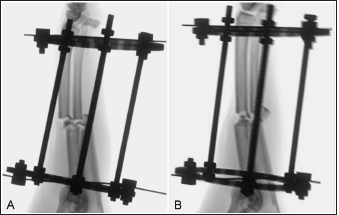

The total procedure time as well as incremental times for the subcategories of fixator placement, reduction, radial approach, and plate application did not differ between the cranial and medial plating groups (Table 1). Placement of the proximal Kirschner wire was more cumbersome than distal wire placement in both plating groups. Proximal cranial-to-caudal Kirschner wire placement was also more challenging than medial-to-lateral wire placement. Wire obliquity had to be addressed in four limbs in the cranial plating group and five limbs in the medial plating group. Obliquity was addressed by placing flat washers on one or both of the fixation bolts securing the Kirschner wire (n=1 limb in each plating group), attaching the fixation wire on opposite surfaces of the ring (n=1 and 2 in the cranial and medial plating group, respectively), or removing and replacing the wire (n=4 and 3 in the cranial and medial plating group, respectively). Lateral translation of the distal fracture segment along the Kirschner wire was performed to improve frontal plane alignment prior to plating in three limbs in the cranial plating group (Fig. 2). Caudal translation of the distal fracture segment along the Kirschner wire was performed to improve sagittal plane alignment prior to plating in two limbs in the medial plating group (Fig. 3). Obtaining sufficient exposure of the proximal radius to allow for plating required substantial tissue dissection, particularly in larger cadavers in both plating groups. The distal ring interfered with establishing a distal-to-proximal epiperiosteal tunnel in one limb in the cranial plating group, necessitating proximal-to-distal development. Plate orientation was more craniomedial than medial in six limbs in the medial plating group. Bone-holding forceps were used to improve reduction and alignment and to maintain appropriate plate position on the radius during plating in five limbs in the cranial plating group and six limbs in the medial plating group. Alignment was also similarly improved using bone holding forceps following initial plate placement by loosening then retightening or removing and replacing screws in four limbs in both plating groups (Fig. 4). The proximal or distal ring interfered with inserting the locking drill guide into the plate in three limbs in both plating groups. The fixator was removed in these limbs to allow placement of the final proximal or distal screw. Total and incremental procedure subcategory Likert scores assessing ease of performance did not differ between plating groups (Table 2). The number of fluoroscopic images (mean ± SEM: 8.7 ± 0.9 and 9.0 ± 0.8 for cranial and medial plating groups, respectively) obtained during the procedure did not differ between plating groups (p =0.77).

Fig. 2. Fluoroscopic images of a limb assigned to the cranial plating group obtained after application of the circular construct. The Kirschner wires were placed from medial to lateral. Note that the distal fracture segment is medially displaced after the radius and ulna had been distracted out to length (A). Manual pressure was applied to the medial aspect of the distal radial segment to translate the segment laterally along the implanted Kirschner wire to improve frontal plane alignment (B).

Fig. 3. Fluoroscopic images of a limb assigned to the medial plating group obtained after the application of the circular construct. The Kirschner wires were placed from cranial to caudal. Note that the distal fracture segment is cranially displaced after the radius and ulna had been distracted out to length (A). Manual pressure was applied to the cranial aspect of the distal radial segment to translate the segment caudally along the implanted Kirschner wire to improve sagittal plane alignment (B).